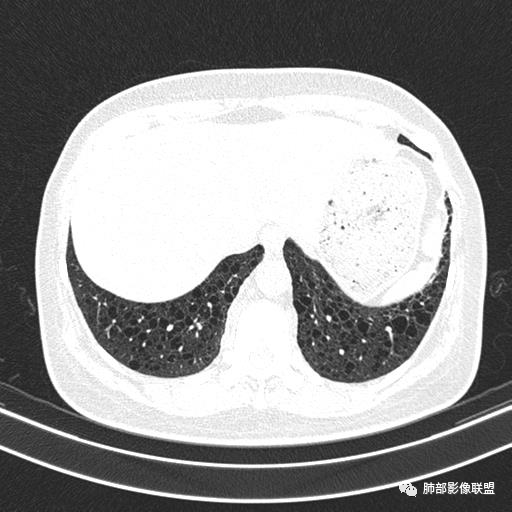

双肺弥漫囊腔,累及肋膈角,囊腔形态相对规则单一。

CT平扫示双肺弥漫分布大小不等囊状薄壁透光区,无内、中、外带分布差异,间质稍示增厚。拟LAM

中年女性育龄期妇女,咳嗽气喘,无吸烟史,有苯吸入史。影像:双肺弥漫均匀小囊腔,无明显分布优势,囊腔形态欠规则,壁薄,部分囊腔边缘血管征,伴双肺弥漫磨玻璃影,无结节,考虑lam,鉴别苯中毒肺损伤,囊腔多有分布优势,小叶中心分布为主,形态规整等

女,46,活动性气喘1年。苯吸入史半年。胸部CT:两肺弥漫囊腔,上至肺尖,下至肋膈角,形态类似小囊腔。考虑:LAM,鉴别LIP,BHD,PLCH等。

CT表现:双肺弥漫大小不等的薄壁囊腔,囊壁<2mm,外形规则,血管影多位于囊腔周围,囊腔之间肺组织正常,随着疾病进展到晚期,囊腔变大、增多,不可胜数,囊腔可融合成较大的囊,与肺气肿相似,形成间质性肺纤维化。部分病例可出现结节影。